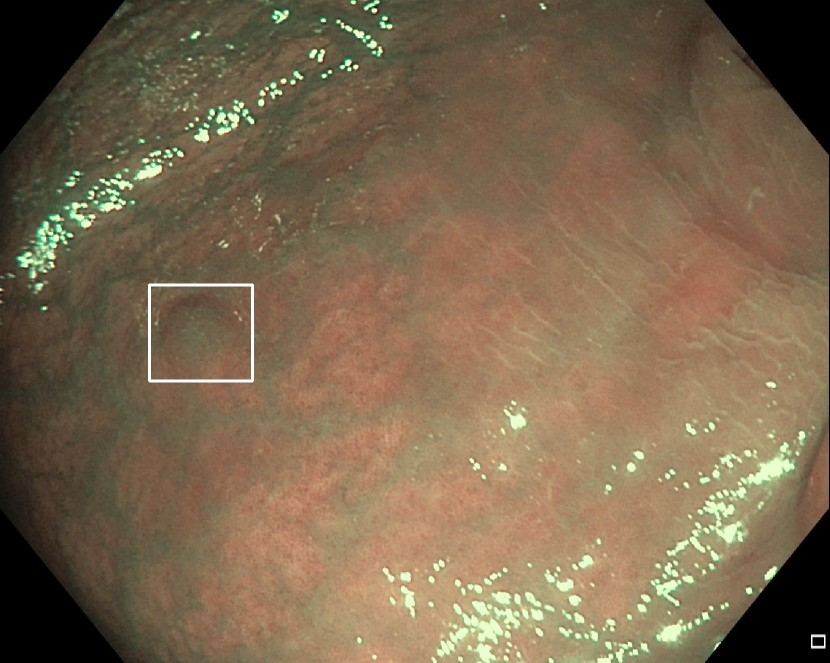

Refer to caption

(f)

Figure 7: Sample images from the testing dataset, with results from the best performing model. White boxes are the ground truth annotations, blue ellipses are the model predictions. In the first row, examples of false negative polyps are shown: (7(a)) a small and distant polyp, (7(b)) a polyp partially covered by water/bubbles, (7(c)) a polyp framed in blue light, (7(d)) a large polyp near the image boundary and overexposed. In the second row, examples of false positive detections are shown: (7(e)) the model activates on a artifact due to stain and motion blur, (7(f)) the model activates on a solid residue, (7(g)) the model activates on an area of the colonic mucosa that is not well inflated, (7(h)) the model activates on a dark and distant area of the colonic mucosa whose shape is similar to a polyp.

Finally, in Figure 7, we display examples of false negatives and false positives from the test set, generated by the best performing model. To visually assess the performance on a whole video, we have uploaded a 60-minute colonoscopy video featuring 6 polyps, the longest in our test set, at https://figshare.com/s/fbb0834a21082984336c (with predictions marked in cyan and ground truth boxes in white). The image examples illustrate how the model struggles with small, occluded, or poorly imaged polyps, and generates false positives in areas that visually resemble polyps, often due to motion or suboptimal imaging. These observations persist throughout the entire video analysis, highlighting the importance of minimizing false positives throughout the entire procedure while maintaining high polyp recall.